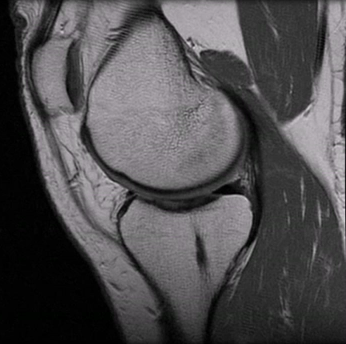

This is an actual MRI of my right knee. No shit.